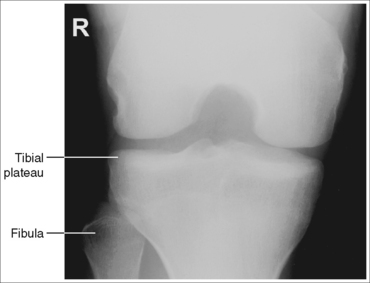

The knee demonstrates an AP projection. The medial and lateral femoral epicondyles are in profile, the femoral condyles are symmetrical, the intercondylar eminence is centered within the intercondylar fossa, and the tibia is superimposed over 0.25 inch (0.6 cm) of the fibular head.

• To obtain an AP knee projection, place the patient in a supine position with the knee fully extended. Internally rotate the leg until an imaginary line drawn between the medial and lateral femoral epicondyles is positioned parallel with the IR (Figure 6-71). This positioning places the medial and lateral femoral epicondyles at equal distances from the IR as well as medially and laterally in profile, respectively. It also centers the intercondylar eminence within the intercondylar fossa and draws the fibular neck and a portion of the fibular head from beneath the tibia.

• Effect of rotation. If the femoral epicondyles are not positioned parallel with the IR, an AP projection has not been obtained. If the patient's leg was not internally rotated enough to place the epicondyles at equal distances from the IR, they are not in profile, the medial femoral condyle appears larger than the lateral condyle, and the tibia is superimposed over more than 0.25 inch (0.6 cm) of the fibular head (see Image 54). If the patient's leg was internally rotated more than needed to place the femoral epicondyles at equal distances from the IR, the epicondyles are not demonstrated in profile, the lateral femoral condyle appears larger than the medial condyle, and the tibia is superimposed over less than 0.25 inch (0.6 cm) of the fibular head (see Image 55).

The knee joint space is open, the anterior and posterior condylar margins of the tibia are superimposed, the intercondylar eminence and tubercles are demonstrated in profile, and the fibular head is demonstrated approximately 0.5 inch (1.25 cm) distal to the tibial plateau.

• The anterior and posterior condylar margins of the tibia are superimposed if the correct central ray angulation, as determined by the patient's upper thigh and buttocks thickness, is used. By studying the tibial plateau region, you will see that the tibial plateau slopes distally approximately 5 degrees from the anterior condylar margin to the posterior condylar margin on both the medial and lateral aspects (Figure 6-72). Only if the central ray is aligned parallel with the tibial plateau slope is an open knee joint space obtained.

• Determining the central ray angulation. When a patient is placed in a supine position, the degree and direction of the central ray angulation required depend on the thickness of the patient's upper thigh and buttocks. This thickness determines how the lower leg and the tibial plateau align with the IR. Figure 6-73 shows a guideline that can be used to determine the central ray angulation for different body sizes; it illustrates the relationship of the tibial plateau to the imaging table as the patient's upper thigh thickness increases. Note that a decrease occurs in femoral decline, and a shift occurs in the direction of the tibial plateau slope as the thickness of the thigh decreases. Because of this plateau shift, the central ray angulation must also be adjusted to keep it parallel with the plateau and to achieve an open knee joint. For optimal AP knee projections, measure from the patient's anterior superior iliac spine (ASIS) to the imaging table on either side to determine the central ray angulation to use for each knee examination. When measuring this distance, do not include the patient's abdominal tissue. Keep the calipers situated laterally next to the ASIS. If the measurement is less than 18 cm, a 5-degree caudal angle should be used. If the measurement is 19 to 24 cm, a perpendicular beam should be used. If the measurement is greater than 24 cm, a 5-degree cephalad angle should be used. Using the correct central ray angulation not only results in an open knee joint space but also provides optimal demonstration of the intercondylar eminence and tubercles without foreshortening.

• Effect of poor central ray angulation. When examining an AP knee projection for which an inaccurate central ray angulation was used, you can determine how to adjust the angulation by judging the shape of the fibular head and its proximity to the tibial plateau. If the fibular head is foreshortened and demonstrated more than 0.5 inch (1.25 cm) distal to the tibial plateau, the cephalad angle was too great (see Image 58). If the fibular head is elongated and demonstrated less than 0.5 inch (1.25 cm) distal to the tibial plateau, the caudad angle was too great (see Image 59).

• Center the central ray to the midline of the knee at a level 1 inch (2.5 cm) distal to the palpable medial epicondyle to place the knee joint in the center of the exposure field. (As long as the knee remains extended, an alternative central ray placement is 0.5 inch (1.25 cm) distal to the patellar apex.) Open the longitudinal collimation enough to include one fourth of the distal femur and proximal lower leg. Transverse collimation should be to within 0.5 inch (1.25 cm) of the knee skin line.

The femoral epicondyles are not in profile, the medial femoral condyle appears larger than the lateral condyle, and the fibular head demonstrates more than 0.25 inch (0.6 cm) of tibial superimposition. The leg was externally rotated.

Internally rotate the leg until the femoral epicondyles are at equal distances from the IR.

The femoral epicondyles are not in profile, the lateral femoral condyle appears larger than the medial condyle, and the fibular head demonstrates less than 0.25 inch (0.6 cm) of tibial superimposition. The leg was internally rotated.

Externally rotate the leg until the femoral epicondyles are at equal distances from the film.